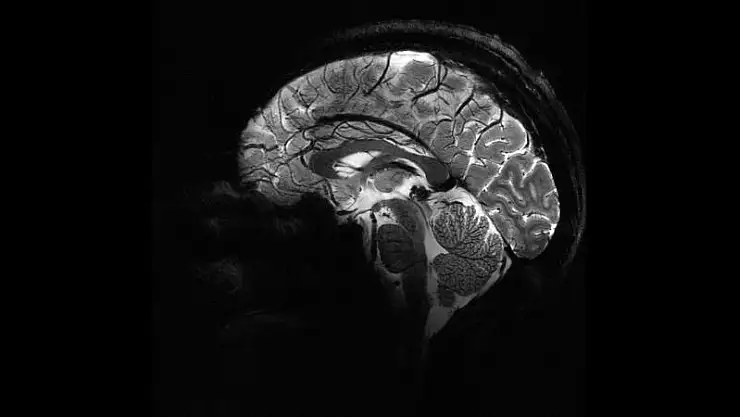

Pandemi beyinleri hızla yaşlandırdı

İngiltere'de yapılan bir araştırmaya göre, COVID-19 döneminde insanların beyinleri 2020 öncesine kıyasla ortalama 5,5 ay daha hızlı yaşlandı.Üstelik bu artış, COVID geçirmeyenlerde de görüldü.

İngiltere’de yapılan bir araştırmaya göre, COVID-19 döneminde insanların beyinleri 2020 öncesine kıyasla ortalama 5,5 ay daha hızlı yaşlandı. Üstelik bu artış, COVID geçirmeyenlerde de görüldü. Uzmanlar değişimlerin tersine dönebileceğini söylüyor.

Nottingham Üniversitesi’nden bilim insanları, UK Biobank’ta yer alan 15 binden fazla yetişkinin verileriyle sağlıklı beyin yaşlanmasını tanıyan bir yapay zekâ modeli geliştirdi. Model, pandemiden önce tarananlarla, önce ve pandemi sırasında taranan iki grubun beyin yaşlarını karşılaştırdı.

Araştırmaya göre, pandemi sürecinde insan beyninin yaşlanma hızı ortalama 5,5 ay öne çekildi.